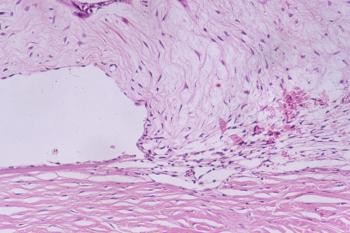

Here the intraocular pressures were

45mmHg in each eye and the condition was glaucoma caused by the bu gene.

Other possibilities might include retrobulbar abscessation, although this

would be rare bilaterally, and venous congestion causing retrobulbar plexus

engorgement, again a very rare condition. The bu gene is common in New

Zealand White rabbits like this one, causing a dysplastic iridocorneal

angle where drainage is very poor. A useful paper on the condition is Ueno

and colleagues report on Histopathological changes in iridocorneal angle of

inherited glaucoma in rabbits. Graefes Arch Clin Exp Ophthalmol.

1999;237:654-60

(c) 2005 Dr David L

Williams